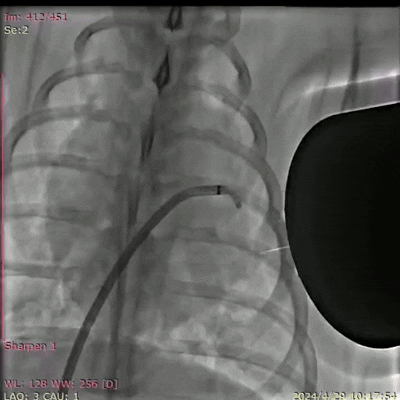

DSA(数字减影血管造影)拍摄的巴马猪体内磁流体左心耳封堵实验过程 深圳先进院供图

研究人员在8头巴拿马猪、30只SD大鼠,以及比格犬的跨物种验证中发现,该材料在实验动物介入手术中无明显出血和心率异常。3D重建显示,新型磁流体机器人能够彻底封堵左心耳血栓,适用于各种复杂形态的左心耳。磁流体机器人在猪模型上植入2至10个月后,固化后的磁凝胶表面可形成光滑完整的心内膜,解剖学显示,无器械相关性血栓形成和心肌损伤,为团队提出的磁流体封堵术的有效性和安全性提供了有力支撑。